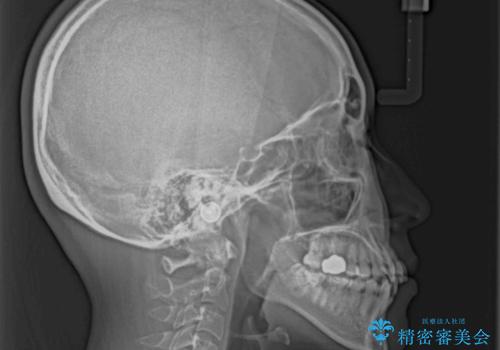

1. 【モニター】急速拡大装置 狭い歯列を拡大してワイヤー装置で短期間治療の治療前